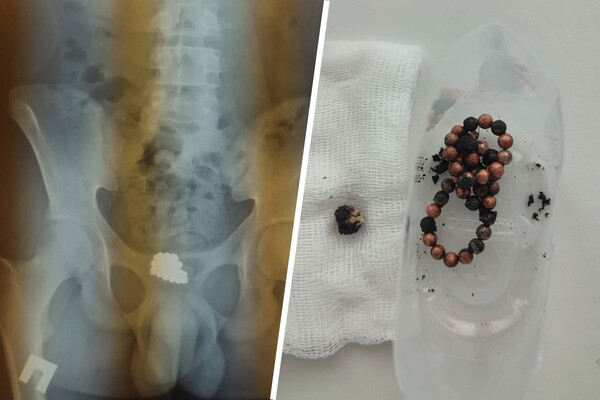

По словам медиков, 16-летний юноша поступил с жалобами на дискомфорт внизу живота. Рентгеновское обследование показало скопление магнитов в мочевом пузыре. Подросток пояснил, что около двух лет назад он сам затолкал в уретру цепочку магнитных шариков, и долгое время об этом не вспоминал.

«В отделении после подтверждения диагноза нашими врачами проведена цистотомия, инородные тела (46 магнитных шариков) удалены из мочевого пузыря», — поделились в пресс-службе больницы.